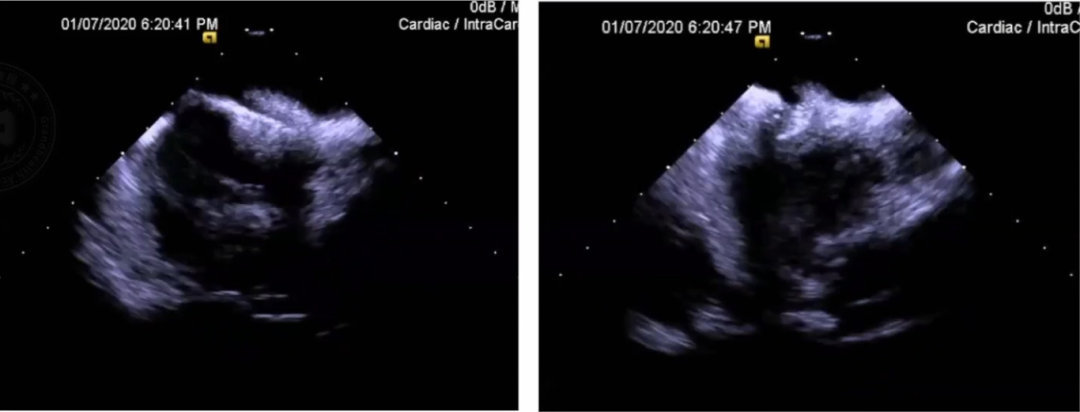

ICE指导PFO封堵

ICE指导PFO封堵与传统术式(TTE&DSA指导PFO封堵)相比,扇面更全、角度更多、更直观,三维PFO定位辅助封堵更精准,减少射线量及射线时间更绿色,避免患者TEE的痛苦(术前术后禁食,食道粘膜损伤),并发症监测更安全。

步骤一:ICE显示FO的导管操作。ICE导管显示Homeview,顺转至LPV扇面(兔耳征),P弯至AO根部出现,R弯至SVC出现,同时展示FO整体形态。

步骤二:ICE下彩色多普勒检查。ICE-P弯结合R/L弯充分暴露FO,术中ICE多普勒检查发现可疑靶点。

步骤三:ICE指导下右心导管过PFO。右心导管锚定靶点,尝试过间隔;注射生理盐水确认已过间隔。

随后导丝置入LSPV,撤导丝后鞘管双轨征。

步骤四:ICE直视置入封堵伞。

步骤五:牵拉实验和彩色多普勒检查。牵拉试验,确保封堵盘位置良好;多普勒确认封堵情况。

步骤六:ICE直视下封堵伞释放和验证。释放鞘管,封堵盘贴合良好;多普勒再次确认;右房注射生理盐水确认封堵状态。